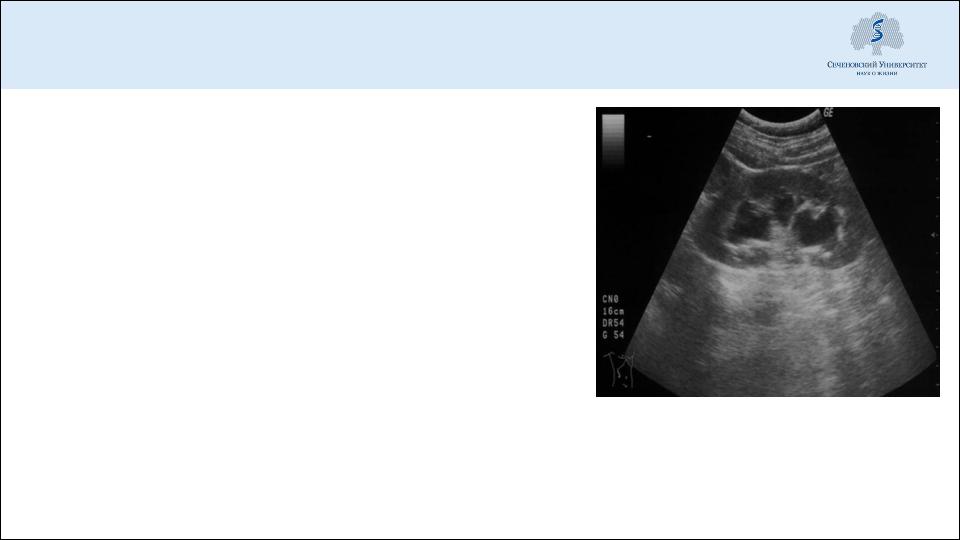

КТ (УЗИ) – утолщение и отек поджелудочной железы

КТ, УЗИ – расширение чашечно-лоханочной системы, конкремент